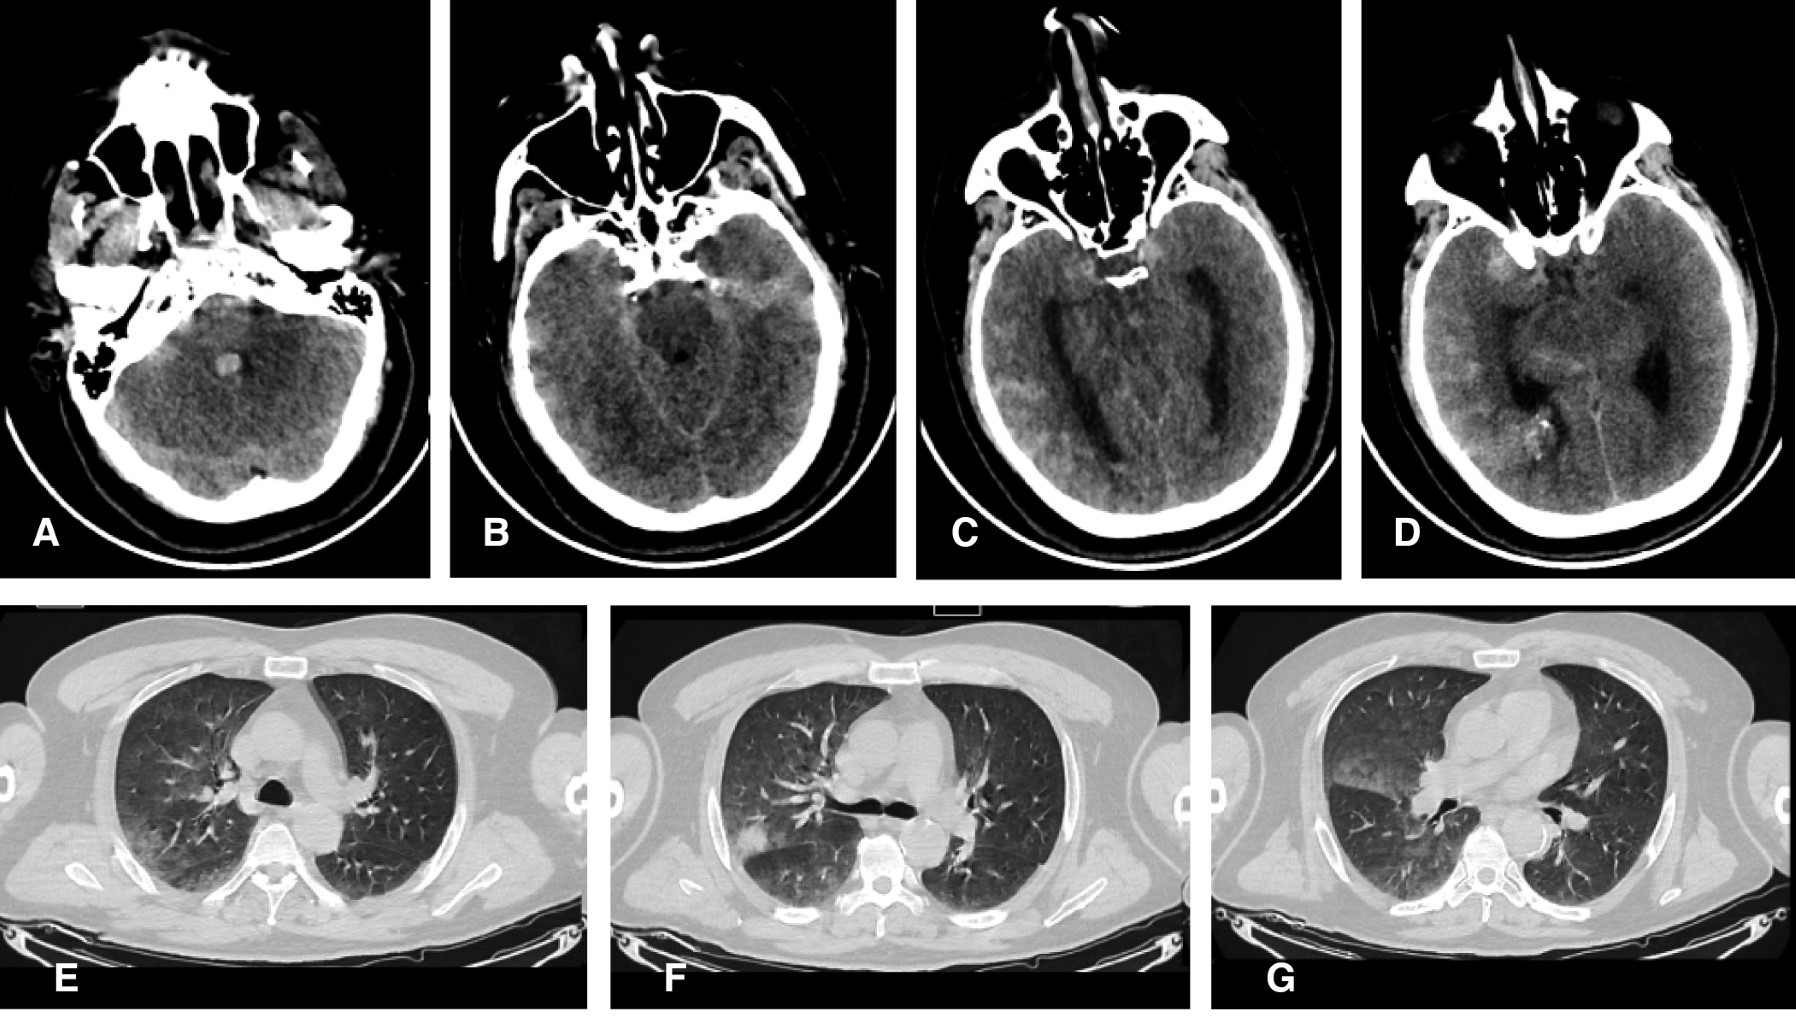

El paciente ingresó a la UCI con APACHE II y SOFA de 17 y 5 puntos, respectivamente. A pesar de iniciar la VMI con PEEP, su PaO2/FiO2 fue de 88 mmHg, la radiografía de tórax mostró un compromiso pulmonar bilateral severo (Figura 3A), por lo cual se inició bloqueador neuromuscular, pronación prolongada (72 horas) en posición Trendelenburg invertido de 30° y parámetros ventilatorios protectivos (volumen tidal 4-8 mL/kg peso predicho, PEEP de acuerdo con el SDRA network, presión meseta < 30 cmH2O, presión de conducción < 15 cmH2O e hipercapnia permisiva) y dexametasona 6 mg/día hasta completar 10 días. Adicionalmente, recibió solución salina hipertónica al 5%, noradrenalina para mantener la presión arterial media entre 80-90 mmHg, nimodipino y se monitorizó el diámetro pupilar bilateral. Añadido a esto, se evitaron la hipoxemia o hiperoxemia, hipotensión o hipertensión arterial, hipotermia o hipertermia, hipoglucemia o hiperglucemia, y la hipocapnia o hipercapnia severa.

En los primeros tres días en UCI hubo una respuesta oxigenatoria favorable sin compromiso pupilar o deterioro hemodinámico, la PaO2/FiO2 máxima alcanzada fue de 210, fue supinado después de cumplir las 72 horas en posición prona. A partir del quinto día en UCI se observó deterioro oxigenatorio progresivo, el cual estuvo asociado a una neumonía tardía que se relacionó al ventilador (NAV) e inició tratamiento antibiótico empírico de amplio espectro. Durante el octavo día en UCI aparecieron nuevos criterios de SDRA moderadamente grave con PaO2/FiO2 de 149 mmHg (Figura 3B). Se inició una segunda sesión de pronación prolongada, que conservó los parámetros ventilatorios y un monitoreo clínico neurológico semejante (Figura 4).

Se obtuvo una respuesta oxigenatoria progresivamente favorable con una PaO2/FiO2 máxima de 230 mmHg sin alteración en la respuesta pupilar, la cual se mantuvo hasta el undécimo día en UCI y entonces se realizó la supinación (Figura 4). Durante su estancia en UCI el paciente cursó con pansinusitis nosocomial, nueva NAV sin SDRA, debilidad del paciente crítico, fue sometido a traqueostomía y se realizó el clipaje del aneurisma cerebral sin intercurrencias perioperatorias. La estancia hospitalaria en la UCI fue de 55 días y la total fue de 61 días; el paciente egresó a su domicilio decanulado y con escala de Rankin modificada (ERm) de 3 puntos.

Figura 3